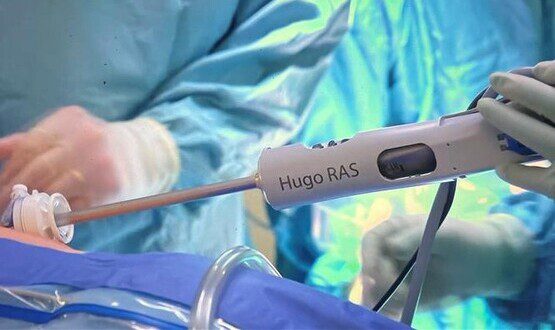

The Double Life: From Hospital Wards to Corporate Meetings. Digital Health Interviews: Austin Chiang

Join us for a captivating conversation with Austin, the Chief Medical Officer at Medtronic Endoscopy. Bridging the world of hands-on medical care and the fast-paced boardrooms of the corporate realm, Austin offers a unique…